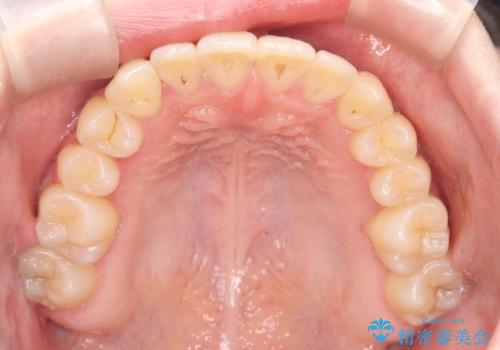

診査の結果、すでに下顎前歯の抜歯が行われていましたが、マウスピースの適合が著しく悪くなっており、歯が計画通りに動いていない状態でした。また、歯を支える骨の厚みや歯肉の薄さを考慮すると、このままマウスピースによる傾斜移動を続けるのは歯肉退縮(歯茎が下がること)のリスクが非常に高いと判断。

装置の変更と歯肉への配慮: ワイヤー矯正は歯の根(歯根)を平行に移動させる「歯体移動」を得意としています。本症例では、歯肉退縮を防ぐために、歯の傾きを精密にコントロールしながら抜歯スペースを閉じる必要がありました。ワイヤー装置を用いることで、インビザラインでは難しくなっていた三次元的な細かい調整を可能にしました。